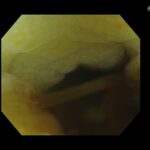

通常光では、癌の同定は困難な症例です。

NBI(癌を見つけやすくするモード)で、癌特有の茶色が、周囲の粘膜(緑)によって、より際立った観察されます。